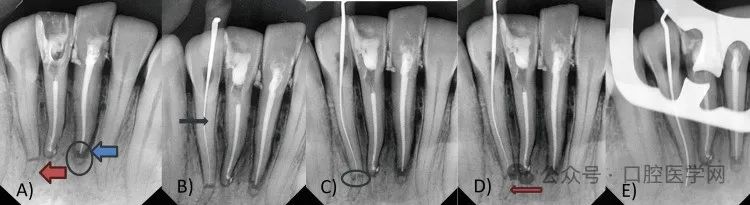

分别对31和42号牙根尖三分之一根折实施根管治疗。对两颗牙齿采用两种不同的非手术创伤处理方法(图4)。

具体方法如下:初级技术中,31号牙保留根尖断端。首先对疼痛更明显的31和41号牙安排根管治疗。使用利多卡因(1:80000)麻醉,橡皮障隔离。为两颗中切牙开髓,用圆钻和Endo Z钻制备三角形髓腔入口。去除牙髓,使用6K、8K、10K、15K锉初步疏通,建立滑行通路。通过数字化放射片及根尖定位仪确定工作长度(31号牙25毫米,41号牙24毫米)。使用润滑剂(乙二胺四乙酸凝胶)配合2.5%次氯酸钠与生理盐水交替冲洗,将根管扩大至30K。使用K锉进行生物力学预备,配合电动马达手机振荡头。初诊时放置氢氧化钙封药。复诊时使用牙胶尖和AH Plus封闭剂(Dentsply)进行充填。采用热垂直加压技术,使用快速充填笔操作。右下中切牙存在侧支开口及唇侧弯曲,根尖部可见封闭剂溢出。左下中切牙根管充填至冠方断端24.3毫米处,未触及根尖断端。根管治疗后使用玻璃离子水门汀(GIC)修复(图5A-5B)。

图5. A) 31和41号牙根管治疗,31号牙保留根尖断端(圆圈及蓝色箭头),42号牙根尖三分之一根折(红色箭头);B) 42号牙冠方断端疏通(黑色箭头);C) 42号牙根折线(圆圈);D) 42号牙根尖断端疏通(红色箭头);E) 42号牙冠方至根尖断端通路

第二种方法采用非手术方式对42号牙冠方与根尖断端进行对位。最初对42号牙采取观察策略,但因患者主诉不适、疼痛及牙齿松动加重,决定实施非手术根管治疗重新连接冠方断端。遵循COVID-19防护措施、患者知情同意及防护技术。对患者实施麻醉,橡皮障隔离。制备髓腔入口,去除冠方断端牙髓。使用25毫米K锉在冠方断端建立初步疏通及滑行通路。冠方断端疏通及预备采用K锉配合电动马达手机振荡头(NSK)。首先仅预备冠方断端,建立直线通路,放置氢氧化钙封药。保留弯曲的根尖断端。三天后患者根管疼痛复发,药物治疗无效。再次检查放射片,推测根尖三分之一断端残留牙髓可能是疼痛持续原因。使用31毫米锉疏通根尖断端,采用直线通路进入牙根冠方至根尖断端。采用平衡力技术冠向下预备确保成形。通过根尖定位仪及影像学分析确定工作长度,使用根管测量尺测量。该牙工作长度约28.30毫米(图6)。

根管扩大使用10K、15K、20K、25K、35K系列K锉。操作时使用振荡头配合Endomate DT电动马达,所有锉转速40,扭矩0。每支锉使用后进行EDTA润滑、2.5%次氯酸钠及生理盐水冲洗。使用牙胶尖和AH Plus封闭剂进行充填。采用热垂直加压技术使用阻塞笔操作。最终使用GIC完成根管治疗后修复(图7)。